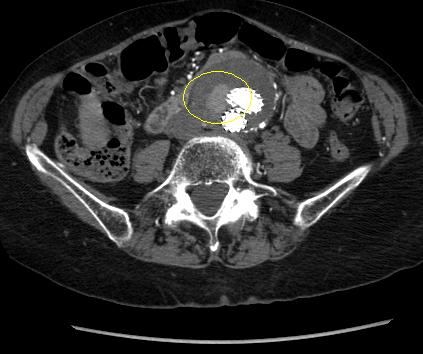

Tipo II:

Fuga persistente de rama.[Figure caption and citation for the preceding image starts]: Endofuga tipo II (marcada con un círculo) descubierta en seguimiento con TCUniversity of Michigan, específicamente los casos del Dr. Upchurch que reflejan los Departamentos de Cirugía Vascular y Radiología [Citation ends].